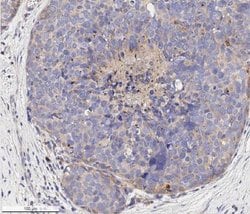

| Immunohistochemistry (Paraffin), Western Blot, Immunocytochemistry | |